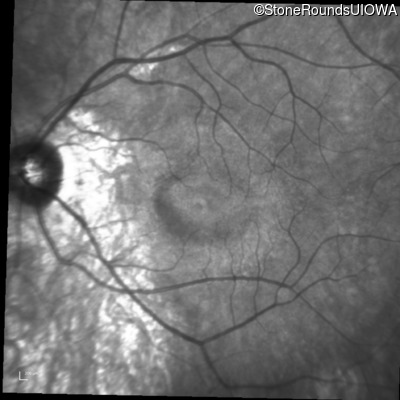

Infrared Fundus Photograph - Left - 20/20 -2

Exemplar